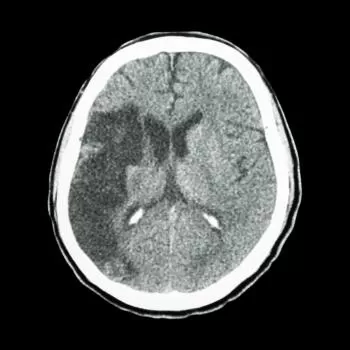

شكل جلطة المخ في الأشعة المقطعية

هناك شكل لجلطة المخ سواء للجلطة الإقفارية أو النزفية وهما كالآتي:

1. الجلطة الإفقارية(Ischemic Stroke) في الأشعة المقطعية

في الأشعة المقطعية، قد يكون من الصعب رؤية شكل جلطة المخ المباشرة، خصوصًا في المراحل الأولى. ومع ذلك، يمكن أن تظهر بعض التغييرات في مناطق المخ المتأثرة بشكل عام، مثل انخفاض في الكثافة الضوئية لهذه المناطق. قد تظهر مناطق معتمة أو غير طبيعية في الصورة، وهذا يشير إلى نقص تروية الدم وضرر في الأنسجة المخية.

2. الجلطة النزفية (Hemorrhagic Stroke) في الأشعة المقطعية:

في حالة جلطة المخ النزفية، يمكن أن يكون من السهل تحديد النزيف أو شكل جلطة المخ في الأشعة المقطعية.

ستظهر منطقة من النسيج المخي بلون أبيض أو فاتح، وهذا يشير إلى وجود الدم. قد يتسبب النزيف في زيادة الضغط داخل الجمجمة مما يؤدي إلى انتفاخ الأنسجة المحيطة، وقد يكون ذلك واضحًا أيضًا في الصورة.

يرجى ملاحظة أن الأشعة المقطعية قد تختلف في قدرتها على رؤية تفاصيل معينة وفقًا للأجهزة والتقنيات المستخدمة، وبالتالي، فإن تقديم تشخيص دقيق يتطلب تقييمًا معمقًا من قبل الأطباء المختصين.

ما هو شكل جلطة المخ في الأشعة؟

شكل جلطة المخ في الأشعة المقطعية أو الرنين المغناطيسي يظهر عادةً كمنطقة رمادية باهتة أو داكنة في الدماغ نتيجة لانخفاض تدفق الدم. يتمكن الطبيب المختص مثل الدكتور أحمد الغيطي من تفسير الصور بدقة لتحديد نوع الجلطة وموقعها وخطورتها.